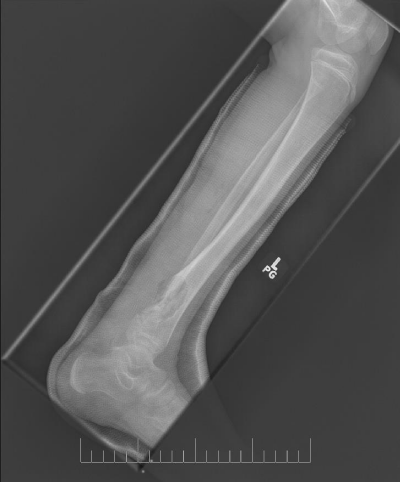

A 10-year-old female presented with left lower leg pain that had progressively increased over the duration of 1 year. On physical examination, tenderness was elicited on palpation of the distal tibia. Routine laboratory testing was normal. X-Ray was performed and revealed a lytic lesion with sclerotic margins in the left lower tibia (Figure 1). MRI was subsequently performed, demonstrating a left lower tibia lesion with low signal intensity on T1 weighted images (Figure 2), and high signal intensity on T2 weighted images (Figure 3). Pathology of the tumor revealed a diagnosis of a CMF. She was treated with curettage and autologous bone grafting (Figure 4). Post op eratively the left leg was immobilized with a plaster cast with restricted weight bearing (Figure 5). Follow up X-ray after 5 years demonstrates no tumor reoccurrence (Figure 6, Figure 7).

Figure 6: 5 year follow up AP X-ray of the left tibia/fibula.